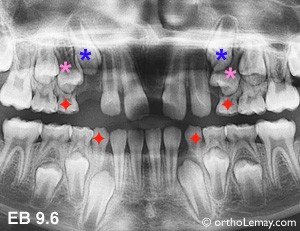

Cas EB : Encombrement et mauvaise direction d’éruption des canines et premières prémolaires supérieures, surtout à gauche. Les extractions aideront les prémolaires supérieures mais aussi les canines inférieures.